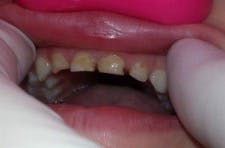

I apply a self-etching bonding agent, light cure, and fill the strip crowns with Activa BioActive-Restorative. I usually seat the central incisor crowns first, light cure, and then seat the laterals. I remove the strip crowns with an explorer, and very little finishing is required. I use Sof-Lex disks (3M) for the incisal and a fluted carbide at the gingival margin if necessary.

This case took less than 20 minutes and looks great (figure 4). Leigh is pleased with his smile and asked if we could fix more teeth. No anesthesia, no tears, and a happy child looking forward to his next visit to the dentist!